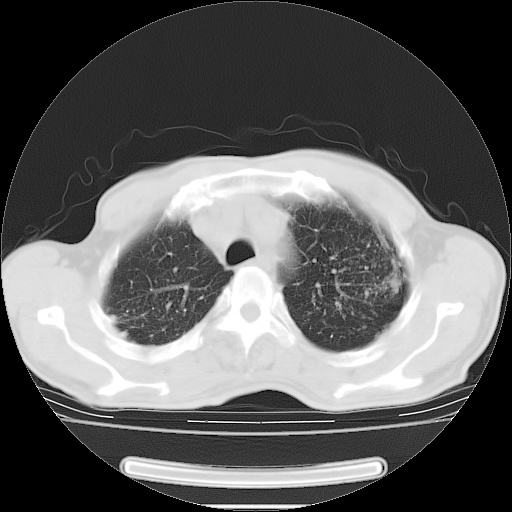

男性患者,63岁。右侧胸背部疼痛2月,加重一周。

考虑:右肺中央型肺癌并右肺下叶不张;两肺尖继发性肺结核。

还有纵隔多处肿大淋巴结及肋骨的改变、两肺多发结节灶。

考虑右中心型肺癌并右下肺不张,肺及纵隔,左肋骨转移。

右肺下叶支气管狭窄闭塞,右下肺不张,气管前间隙淋巴结肿大,两上肺散在分部粟粒灶,沿肺血管支气管束分部,血管支气管束走形较为光滑。考虑右肺中心型肺癌合并肺不张,纵隔淋巴结转移,两上肺癌性淋巴管炎

右肺下叶中心性肺癌并纵隔淋巴结转移,左侧肋骨转移。双肺上叶继发性结核表现。

1)右肺下叶中心性肺癌并纵隔淋巴结转移,两肺转移,左侧肋骨转移。2)双肺上叶继发性结核。

右肺下叶中心性肺癌并纵隔淋巴结及两肺、左侧肋骨转移。双肺上叶继发性结核表现。